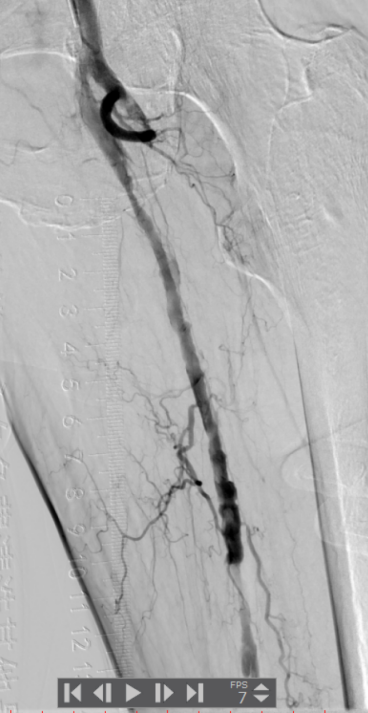

2.使用Rotarex导管由近至远进行血栓抽吸,少量血栓残留,置入溶栓管溶栓。

▲血栓清除后管腔获得较满意,仍有少量残留血栓